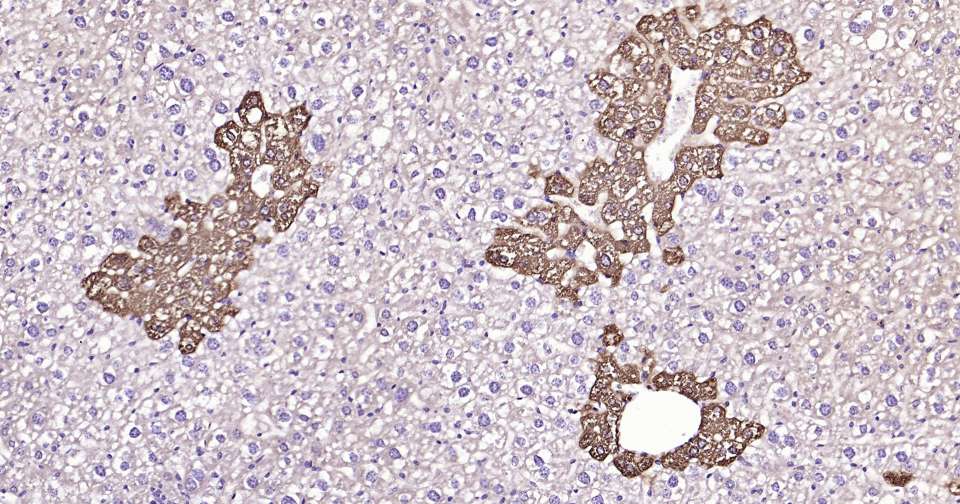

Immunohistochemical analysis of paraffin embedded mouse liver tissue slide using IHC0333 (Glutamine synthetase Kit).

Immunohistochemical analysis of paraffin embedded human liver tissue slide using IHC0333 (Glutamine synthetase Kit).

Immunohistochemical analysis of paraffin embedded rat kidney tissue slide using IHC0333 (Glutamine synthetase Kit).